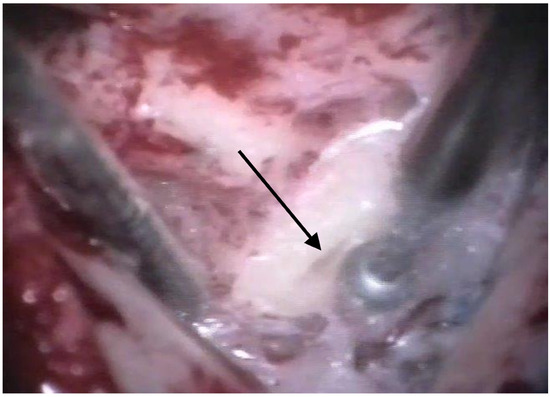

The patients were treated between August 2013 and October 2015 using the identical surgical technique of one-stage cochlear implantation and the occlusion of all three ipsilateral semi-circular canals. For cochlear implantation, a posterior tympanotomy and a round window approach were chosen [14]. Occlusion of the three semi-circular canals was performed before the implantation by reducing the drill speed to 10,000/min. The labyrinth was skeletonized to identify all semi-circular canals. The superior bony layer of the semi-circular canal was drilled down with a diamond burr (2.3 mm) until the endolymphatic duct shone through the last bony layer (blue lining) (Figure 1 and Figure 2). Leaving the endolymphatic duct intact, the temporalis fascia was pushed down in the canal. After sealing with fascia, the canal was filled with bone wax (Figure 3). The area of each canal was covered afterward with a muscle patch and bone pate. Finally, the sealing patch was secured with fibrin glue (Figure 4) [5,15].

Figure 3. Occlusion with bone wax. The arrow points to the wax applied to the canal.